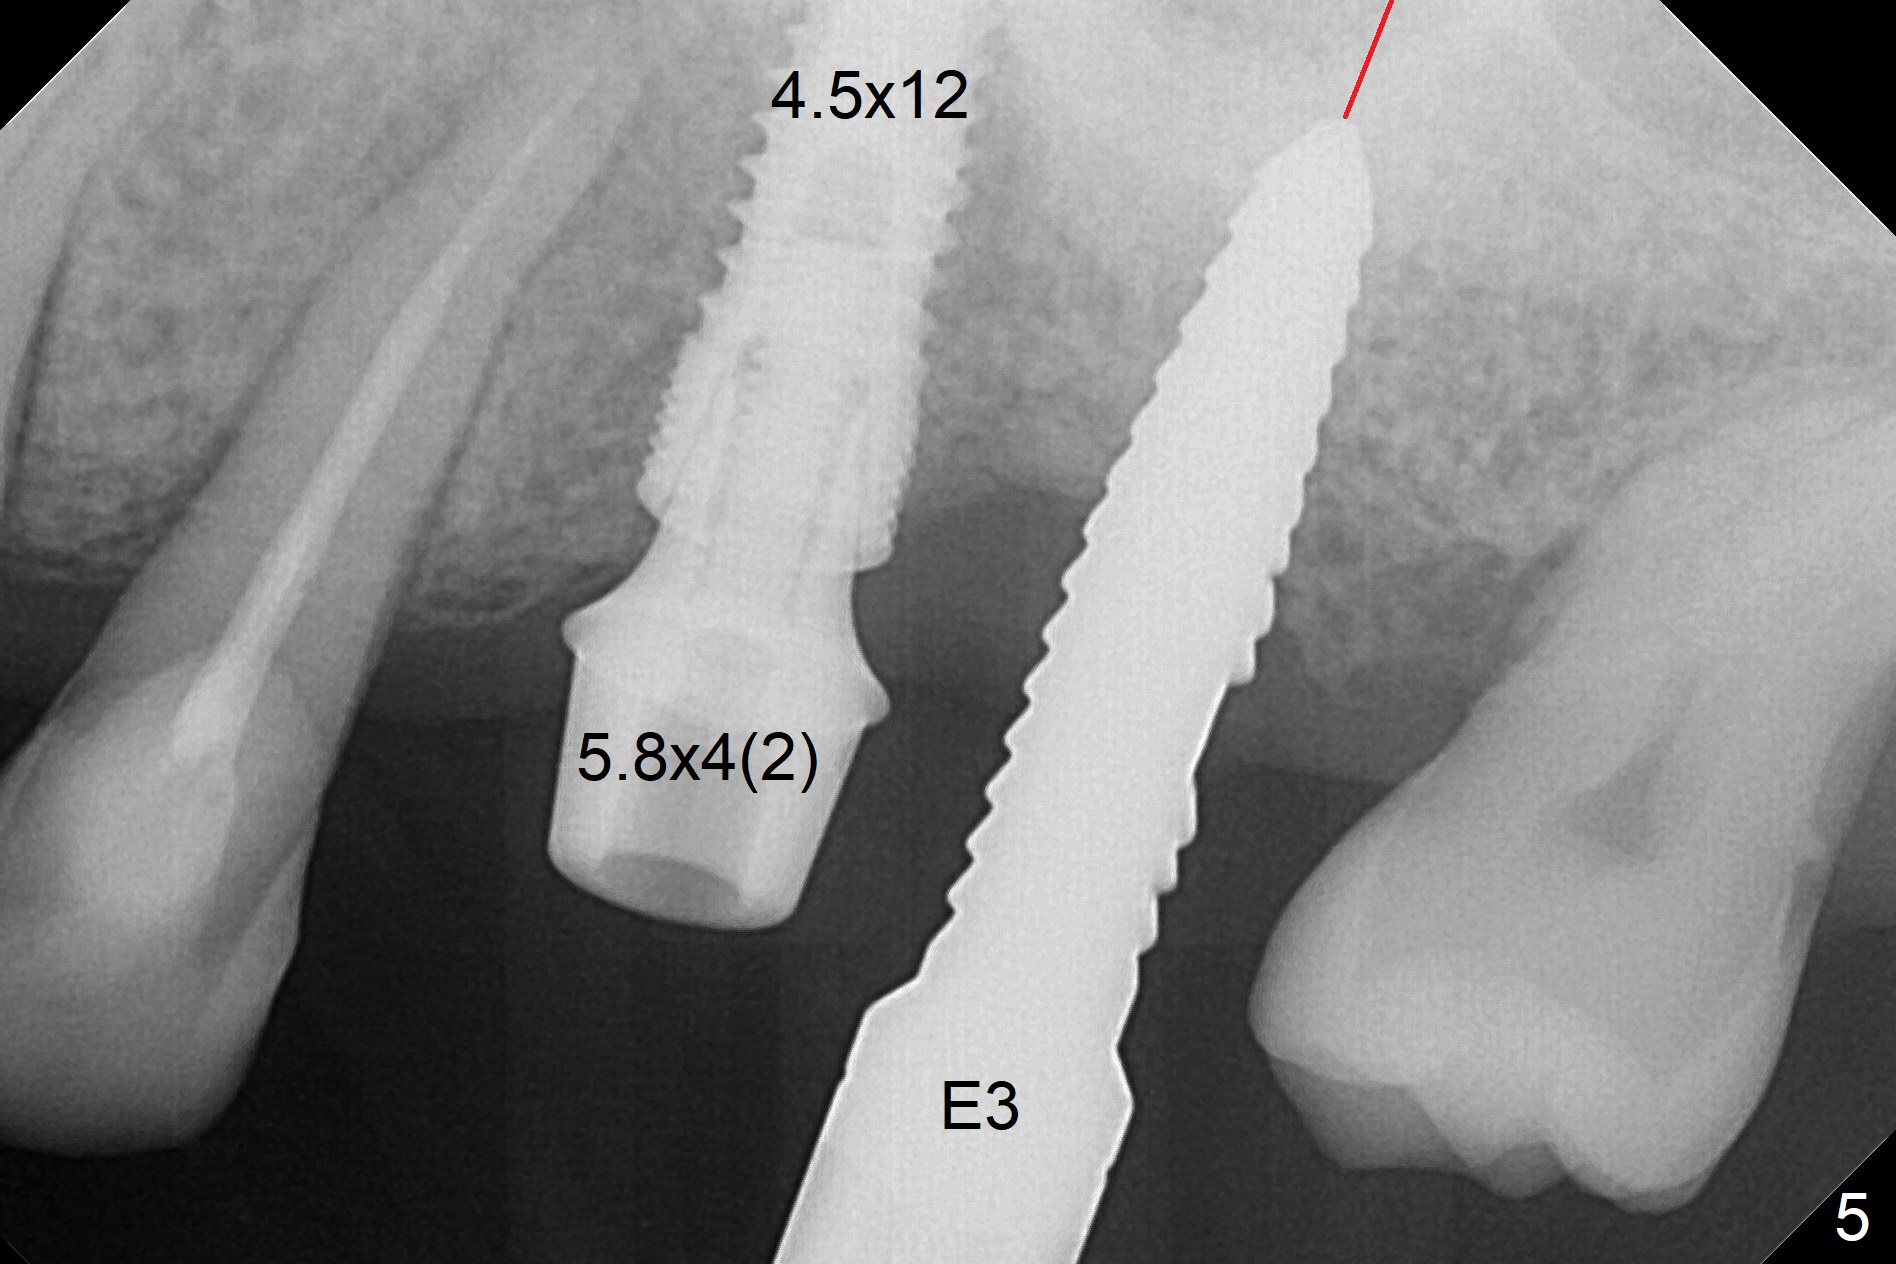

When 1.2 mm drill is used for osteotomy at #14 and 15, the bone feels to be soft (Fig.1). After change in trajectory (Fig.2), Expander 1 (Fig.3: E1, 1/1.6 mm) can be inserted at #14 and 15, while E2 (1.2/2.3 mm) cannot at full length at #14, suggesting hard bone. Osteotomy continues with drills until 4.1x14 mm, followed by insertion of E4 (2.4/3.7 mm) at #14, while osteotomy goes on until E3 (1.7/3.1 mm) at #15 (Fig.4). A 4.5x12 mm SM implant is placed with 50 Ncm (with insertion of a 5.8x4(2) mm abutment as a guide for #15 osteotomy, Fig.5). The apical portion of the osteotomy at #15 (Fig.5 red line) is finished with drills, leading to placement of a 4.5x12 mm implant (>50 Ncm) and 4.8x4(2) mm abutment (Fig.6). With bone density is more than 200 units, bone expansion appears to be not indicated. The patient returns for #13-15 crown prep 4.5 months postop (Fig.7). Abutments change to 5.8x5(3) and 5.8x4(3) mm at #14 and 15, respectively with mesial reduction of the tooth #16 (curved line) before impression. Minimal bone loss is observed 1 year 5 month post cementation (Fig.8,9), thanks to pre-existing wide bone.